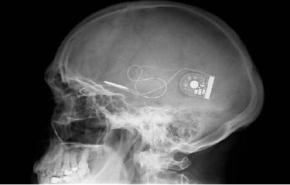

دراسة: تناول الإسبرين بانتظام يؤدي إلى ضعف البصر قالت دراسة استرالية بحثت في معلومات جمعت على مدى 15 عاما ان تناول قرص أسبرين على الاقل أسبوعيا يرتبط بالاصابة بضعف البصر المرتبط بكبر السن.

وكتب الباحثون في دورية جاما للطب الباطني انه حاليا يجري استهلاك أكثر من 100 مليار قرص أسبرين سنويا. ويشيع استخدام الاسبرين للوقاية من النوبات القلبية أو السكتات الدماغية.

وفي عام 2011 خلصت دراسة أوروبية الى أن كبار السن الذين تناولوا الاسبرين يوميا أكثر عرضة بمقدار الضعفين للاصابة بضعف البصر مثل الضمور البقعي مقارنة بأولئك الذين لم يفعلوا ذلك مما دفع المشرفة على الدراسة الجديدة جي جين وانغ الى محاولة تأكيد هذه النتائج.

وحصلت وانغ من جامعة سيدني وزملاؤها على معلومات عن 2389 شخصا تتجاوز اعمارهم 45 عاما. ومن بين هؤلاء قال 257 شخصا انهم تناولوا الاسبرين مرة أسبوعيا على الاقل. وفي نهاية الدراسة اصييب 63 شخصا بما يسمى الضمور البقعي الرطب وهو النوع الاكثر حدة. واصيب 8ر5 في المئة من مستخدمي الاسبرين بانتظام بفقدان الرؤية مقارنة باصابة 3ر2 في المئة من الاشخاص الذين لم يتناولوا الاسبرين بشكل منتظم.

وكتبت وانغ وزملاؤها "يرتبط استخدام الاسبرين بانتظام بزيادة خطر الضمور البقعي الرطب المرتبط بكبر السن بعيدا عن تاريخ أمراض القلب والشرايين والتدخين." وعلى الرغم من ذلك حذروا من أنه لا توجد أدلة كافية تفيد بأن تناول الاسبرين يؤدي الى هذه الحالة. وقالت وانغ "ما زلنا بحاجة لجمع المزيد من الادلة."